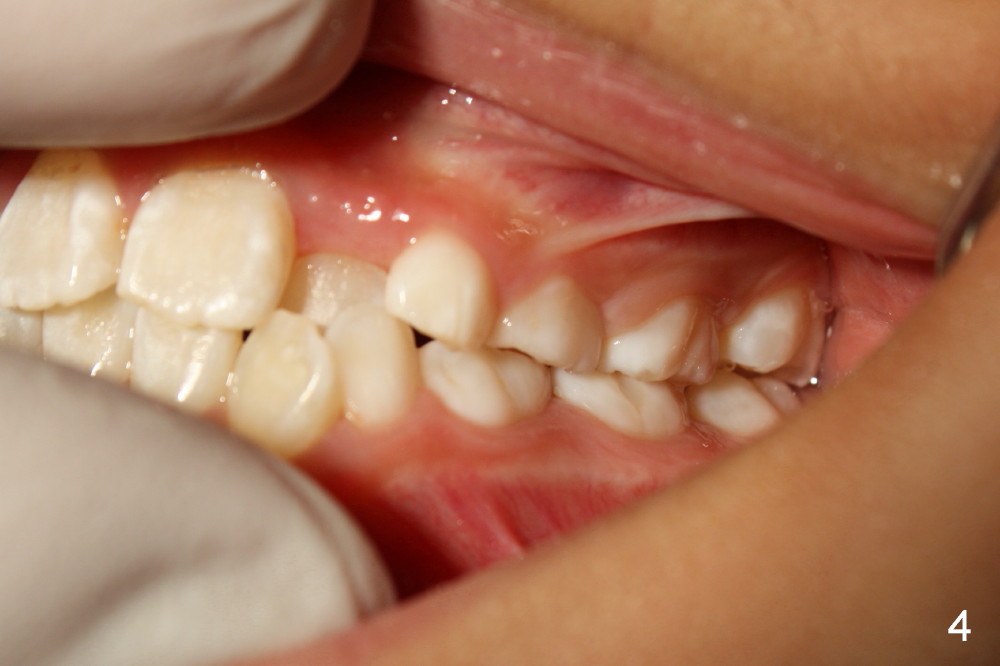

Six months earlier, the tooth #7 is erupting lingually. Now at the age of 8, both of the upper lateral incisors are in cross bite (Fig.1*). It appears that the cross bite is due to jaw deficiency in anteroposterior direction. In fact, these two laterals are blocked because there is not enough space transversely (Fig.2). Posterior occlusion is Class I bilaterally (Fig.3,4). The lower incisors are also crowded. Therefore early comprehensive orthodontic treatment has the most important component: palatal expander. In our previous case, unilateral cross bite resolves rapidly after the palate is expanded.